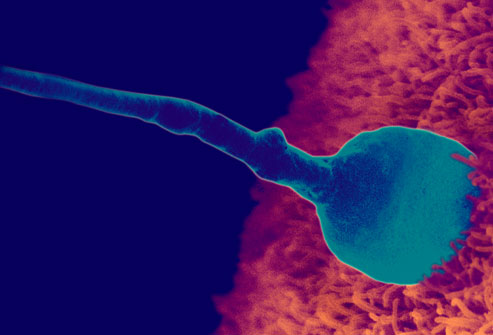

One of the common problems subfertile couple faced is the issue concerning sperm quality and quantity. In the past, male issue had deemed to be responsible for 15-20% of the reason for subfertility. However, over the last 10 years, this issue had become more prevalent and it is estimated that around 40-50% of couples are suffering from male fertility issues.

A recent study in French men between 1989 and 2005 found a significant widespread declines in sperm quality , with average sperm counts falling while percentages of abnormally formed sperm rose. These findings are a “serious public health warning,” the authors wrote. The same findings were observed world wide suggesting a global decline in male fertility.

Despite the lack of awareness, male infertility is a common problem, affecting 1 in 20 men. And among married couples struggling with infertility, 40% of the cases may be attributed to the man. Though it has been extensively studied, male infertility remains a complex problem and the underlying causes are usually unknown. However, a study by researchers at the University of Southern California (USC) has suggested that the underlying cause for male infertility is epigenetics – the way that DNA is processed and expressed.

To identify the link between epigenetic modification and male infertility, USC researchers studied the epigenetic state of DNA from semen samples of male patients at an infertility clinic. Their findings showed that, “Sperm DNA from men with low sperm counts or abnormal sperm had high levels of methylation. However, DNA from normal sperm samples showed no abnormalities of methylation.”